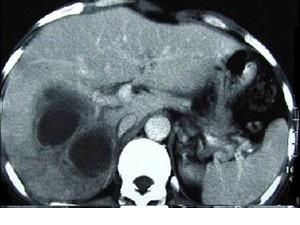

问题 男,45岁,右上腹痛,有发热,白细胞计数升高,CT检查如图,最可能诊断是 ( )

选项 A、肝黄色肉芽肿 B、肝转移癌 C、肝包虫病 D、肝脓肿 E、原发性肝癌

答案 D